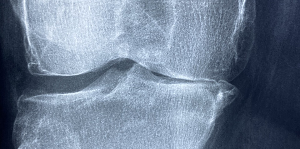

특히 무릎 관절염은 일반적으로 무릎에 생기는 퇴행성 관절염을 의미하는데 가장 흔하게 생기는 관절염으로 전 인구의 10~15%가 앍고 있다고 알려져 있는 정도로 흔한 질병이며 최근 노령화로 인해 무릎 관절염을 겪는 사람이 늘어나고 있다고 합니다.